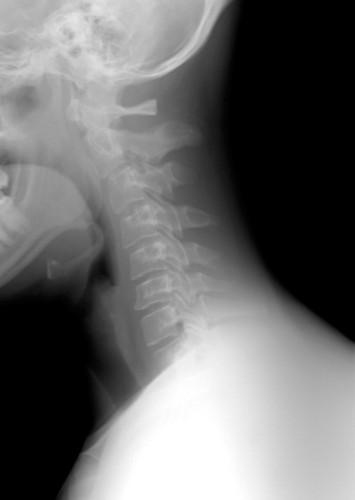

Myélopathie cervicale

La myélopathie cervicale est souvent et fréquemment due à des causes dégénératives. Cette maladie est localisée au niveau des vertèbres cervicales et correspond à une atteinte de la moelle épinière.

La myélopathie correspond à un dysfonctionnement de la moelle épinière. Dans le cas de la myélopathie cervicale, nous parlons donc d’un dysfonctionnement de la moelle épinière localisée au niveau des vertèbres cervicales.

Le canal cervical se rétrécit et provoque une compression chronique de la moelle épinière et une incapacité neurologique. Cela devient alors une myélopathie cervico-arthrosique

Dans la plupart des cas, la myélopathie cervicale apparaît à la suite d’un vieillissement de la colonne vertébrale cervicale engendrant des lésions dégénératives. Ces lésions dégénératives entraînent une compression de la moelle épinière par le rétrécissement du canal rachidien central.